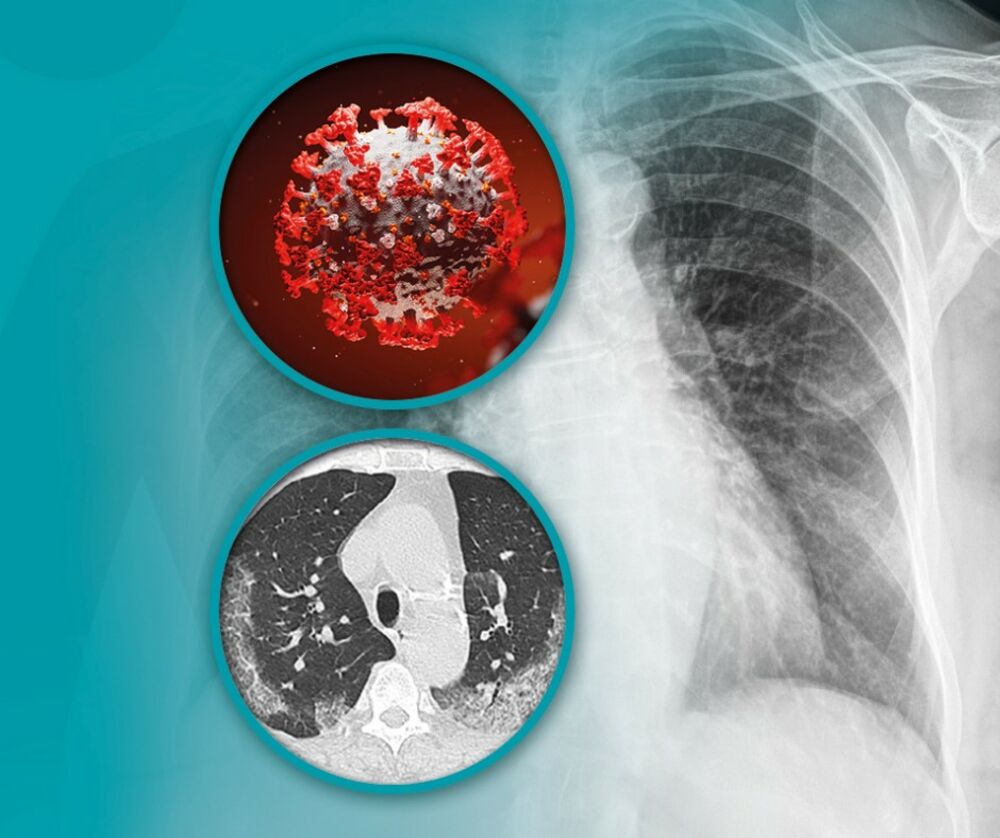

Pokazalo se da su pluća jedan od najugroženijih organa kod pacijenata koji boluju od kovida, a jedan od najpouzdanijih načina za detekciju promena nastalih pod uticajem ove bolesti su savremeni CT skeneri. Uz korišćenje veštačke inteligencije prilikom postavljanja dijagnoze, ovo su jedini uređaji za snimanje pluća koji mogu pouzdano da detektuju ne samo aktivne promene, već i posledice nakon preležane bolesti.

Multidetektorski CT skeneri su jedini uređaji za snimanje pluća koji mogu pouzdano da detektuju ne samo aktivne promene, već i posledice nakon preležane bolesti. Pored toga, ova tehnologija nudi mogućnost snimanja pluća sa presecima na jedan milimetar, što značajno doprinosi detektovanju svega što može da bude važno, kako za pacijente sa aktivnom kovid infekcijom, tako i za one koji su u međuvremenu ozdravili.

Pacijentima je takođe na raspolaganju i poseban program za veštačku inteligenciju RADLogics, koji omogućava obradu snimaka dobijenih na skeneru. Ovaj oblik veštačke inteligencije, potpuno objektivno, precizno i sigurno otkriva promene na plućima karakteristične za COVID 19 infekciju.